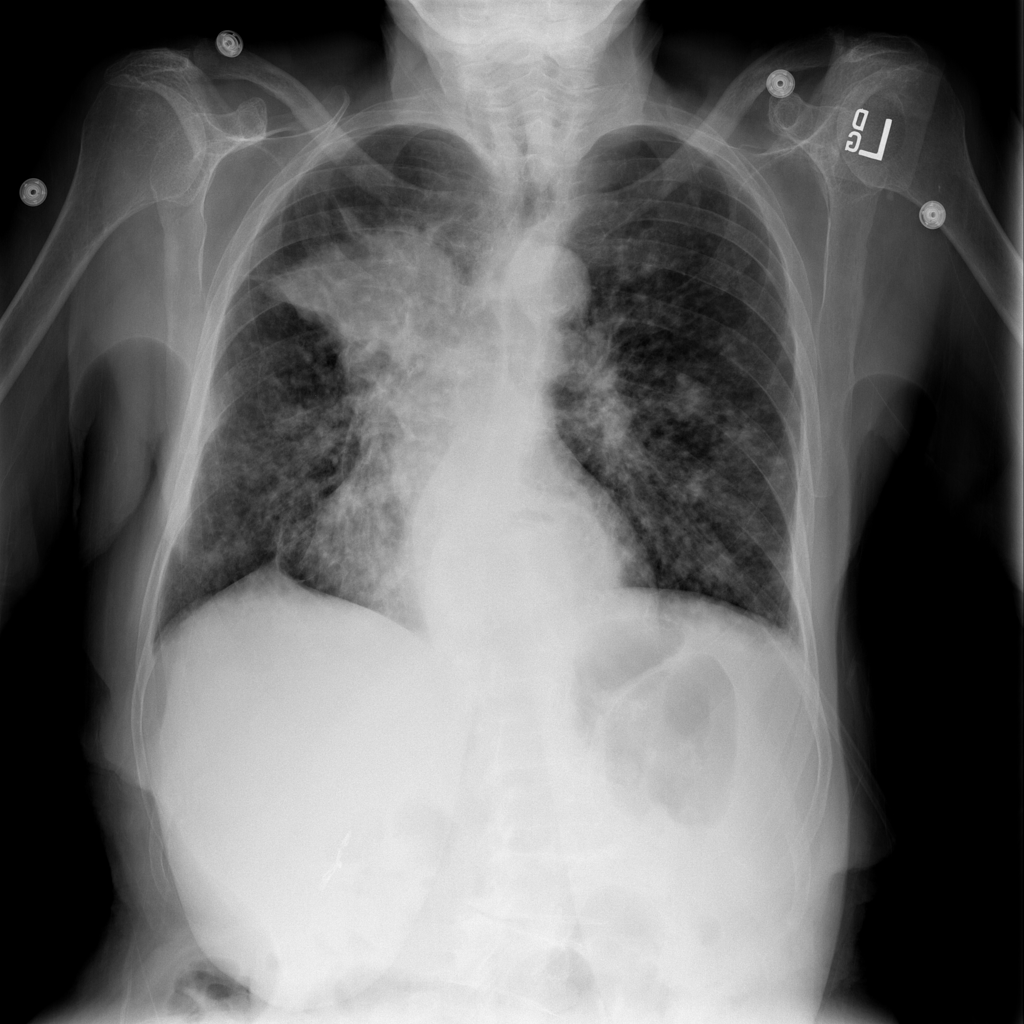

PAT-C048 · IMG-001Hernia

PAT-C048 · IMG-001

PA